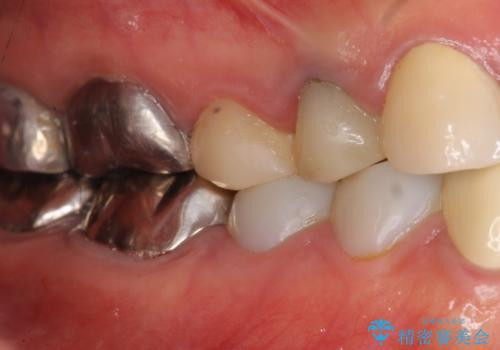

被せ物を入れたばかりの歯が痛む 40代女性

- 他院で被せ物を入れたばかりの歯が痛むことを主訴に来院された患者様です。

「様子を見ましょう」と言われ何もしてもらえず、痛みが続き不安になってしまったとのことでした。

精査したところ、被せ物を入れたばかりの右下の小臼歯(右下5)は不可逆性歯髄炎により神経をとる処置(抜髄)が必要な状態でした。

根管治療後、セラミッククラウンによる補綴治療を行いました。